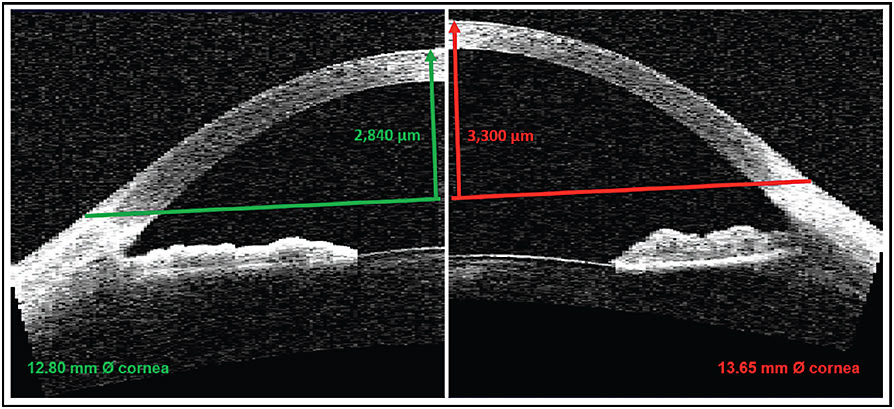

A “typical” eye with an HVID of 11.90mm, radius of curvature of 7.85mm, and an eccentricity of 0.55 (and assuming a scleral radius of 18.0mm over a 15.0mm chord) would have a theoretical ocular sagittal height of 3,150 microns. A variation in corneal diameter of only 1mm either way results in very different sagittal heights of 2,880 and 3,510 microns for corneal diameters of 10.90mm and 12.90mm, respectively—a difference of approximately 630 microns between the two extremes. Figure 3 shows differences in sagittal height for two corneas of the same radius of curvature but differing corneal diameter.

Figure 3. Corneal sagittal height for corneas of the same central radius of curvature (7.85mm), but differing corneal diameters.